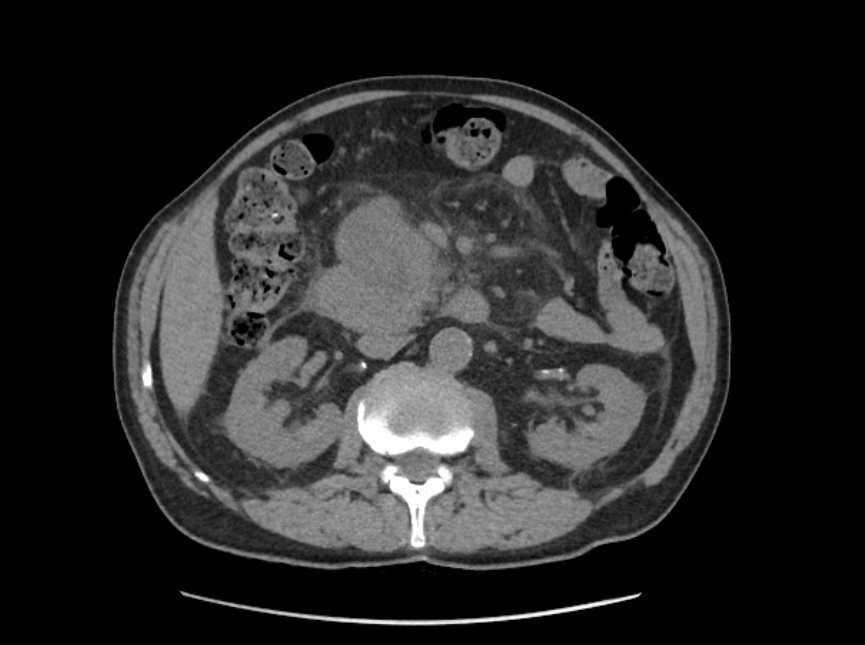

La litiasis y la dilatación de la vesícula biliar encontrada en la ecografía clínica no justificaba todo el cuadro, por lo que solicitamos ecografía reglada al equipo de radiología. En ella informan marcada dilatación de la vía biliar intrahepática, con un colédoco de hasta 15 mm, y estructura mamelonada de aproximadamente 7 cm en cabeza pancreática. Se completa estudio con Tomografía Axial Computarizada que confirma masa en cabeza pancreática compatible con adenocarcinoma que condiciona dilatación de la vía biliar retrógrada.